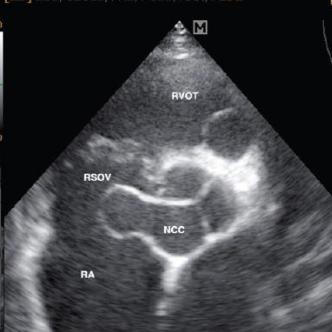

Describe Sinus of Valsalva Aneurysm (SVA)

rare congenital anomaly seen on PSAX or PLAX

not medical emergency because born with it! → still report

weakening or absence of the media layer

weakened sinus dilates and forms an aneurysm, can cause holes

What are some complications of SVA (3)

LSOVA

may rupture into LA or RA

NCSOVA

may rupture into LA, RA, LV, or ventricular septum

RSOVA (most common)

may rupture into LV, RA, RV (across septum), pericardium, adjacent main pulmonary artery

can cause most problems: obstruction, dissection, compression, acute MI, heart block, tamponade

Overall: more blood is being moved back into the heart instead of being pumped out